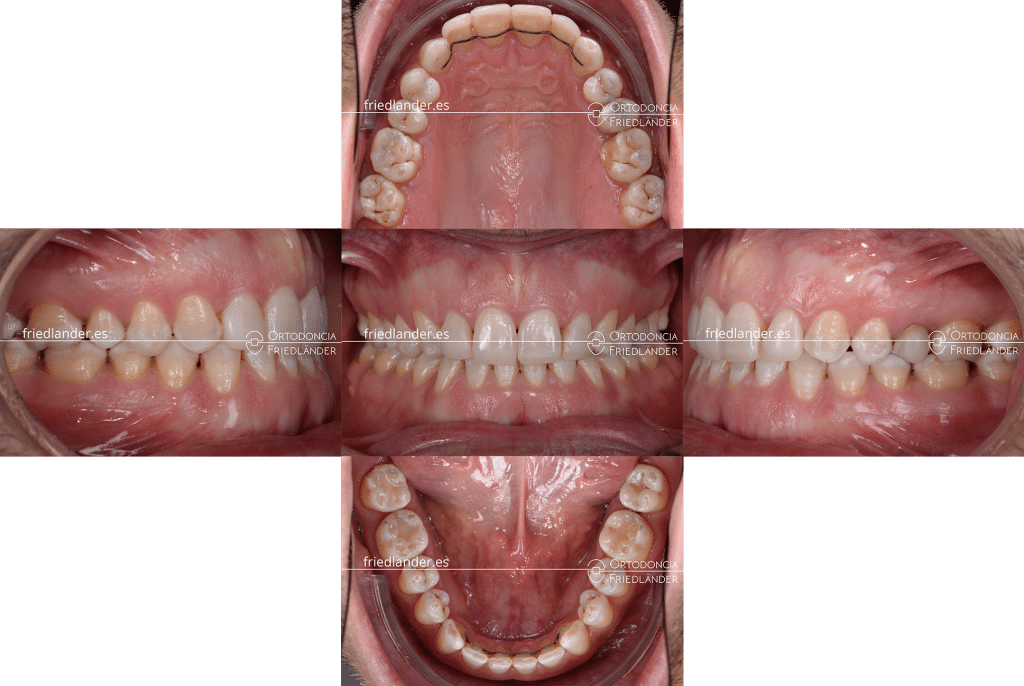

Resultado final del tratamiento de ortodoncia

Los resultados después de unos 20 meses de tratamiento son buenos, la mordida esta cerrada y el engranaje de los dientes posteriores es bueno.

Hemos añadido un poco de composite en los dientes desgastados para mejorar el engranaje de los dientes